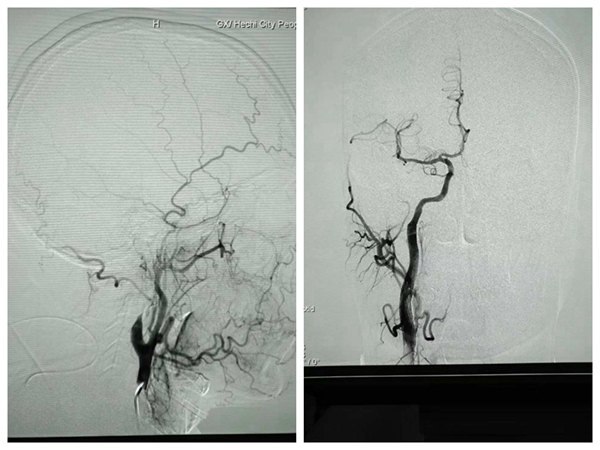

据了解,12月5日上午6点左右,家住南丹车河镇的韦先生在家中突发言语不清、左侧肢体无力,无法自行站立,这突如其来的情况让韦先生及其家人束手无策,随后在左邻右舍的帮助下被送至当地卫生院,医生检查后考虑为脑卒中,因当地医疗条件有限,便联系了我院急诊科,卒中中心立即启动“绿色通道”,在患者到达急诊科时通过专属卒中中心绿色通道进行救治。急诊头颅CT 提示为急性脑栓塞,神经内科一病区韦仕荣主任通过急诊检查结果及结合病人的体征指出:患者病情危重,左侧肢体偏瘫严重,患者定位右侧大脑半球,责任血管为右侧大脑中动脉,右颈内动脉起始部夹层形成并次全闭塞,目前发病已是第5个小时,溶栓出血风险大,必须立即行急诊手术!

一键启动紧急救治预案,所有科室准备就绪,多学科联合配合默契,过床、心电监护、穿刺、造影、支架植入......当天下午14:00两枚救命的支架顺利植入韦先生体内,血管得以开通。术后当日,韦先生神志清醒,言语较前明显清晰,左侧上肢肌力从术前1级恢复至3级,左侧下肢肌力由3级恢复至4级。术后第二天,便可自行起床,术后第三天,可以在走廊慢慢行走。目前韦先生已康复出院。